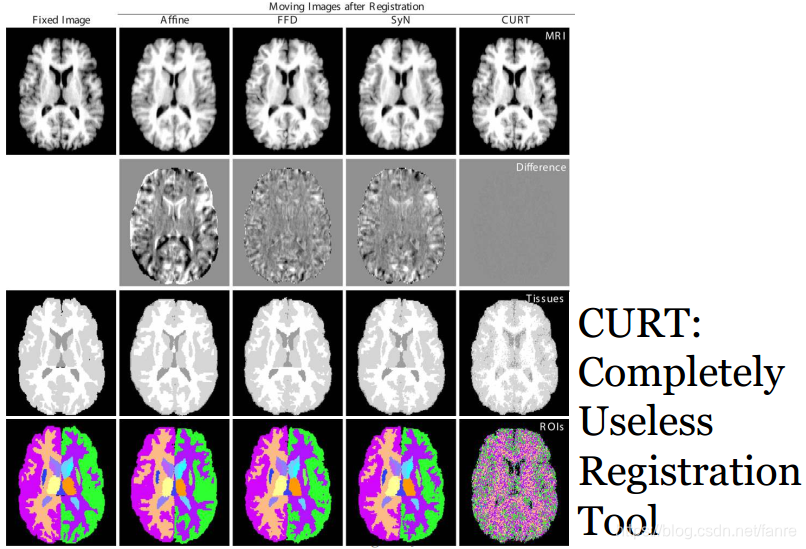

需要真么复杂的处理么?

非常简单的形变配准算法:CURT

基于闭型解的非刚性配准算法来最大化秩相关约束Rank Correlation criterion。图像相似度和组织重叠度来的评价标准更好image similarity and tissue overlap scores。不需要仿射变换处理。